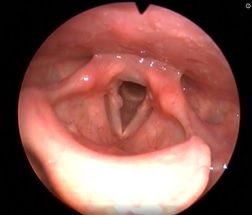

Рис 2А. Двусторонний паралич гортани. До операции.

Рис 2Б Двусторонний паралич гортани. 7 сутки после операции